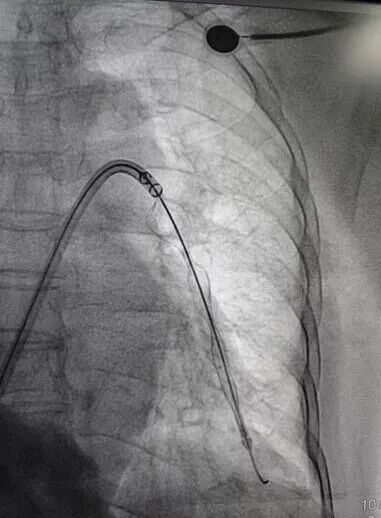

调整导丝至右下肺动脉,再次送入肺动脉取栓支架系统于右下肺动脉行取栓术,可取出较多暗红色血栓。复查造影提示右下肺动脉未见明显血栓,血流明显改善,测得肺动脉压力26/2mmHg。撤出血栓抽吸导管,于下腔静脉造影明确肾静脉位置腰1椎体下缘水平,在肾静脉位置以下成功置入下腔静脉可回收滤器,复查造影示下腔静脉可回收滤器位置正常。